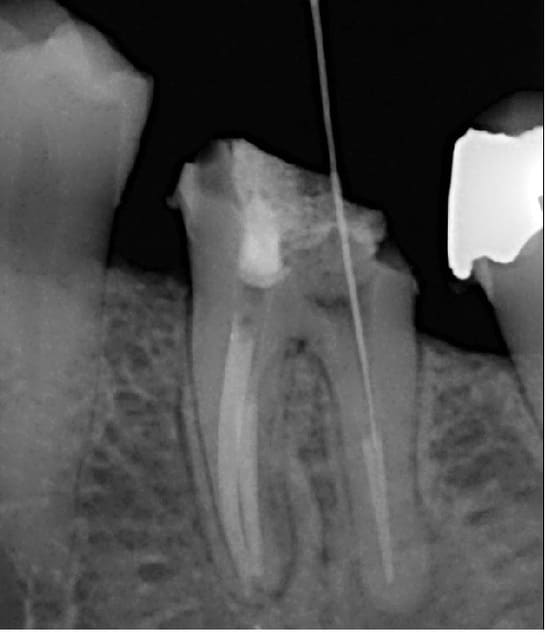

Je me permet de vous demander un conseil; suite à la découverte d'une image sur une 36 je me suis lancé dans la dépose et le retraitement, sauf que je ne progresse absolument pas... J'utilise les protapers de retraitement et rien ne se passe, malgré tous les solvants essayés : essence d'orange, eucalyptus ou rockle's (acétate de dexaméthasone).

Le canal est large, bien droit, avec un ET25 sous contrôle visuel c'est sans problème.

1/ Ce n'est sûrement pas avec le genre de lime qu'il y a sur la radio que tu va progresser

2/ Il faut commencer par éliminer toute la pâte/ciment mécaniquement,au dessus du niveau de progression de cette lime

3/ une radio sans digue dans ces conditions, c'est une chance supplémentaire d'ensemencer le canal et d'aggraver encore la situation

4/ il est possible que le canal soit plat et qu'il soit perméable sur le côté et pas au milieu

Comme Neb: inserts ultrasons satelec ET20 ou ET25 + bon éclairage (et si possible aide optique) pour voir où on va et ça devrai passer.

Par contre, le canal est surement ovale ou plat ce qui expliquerait la pêche à cause d'une zone non obturée.

Edit: en fait je pencherai plutôt pour un delta apical qu'on devine sur la radio.